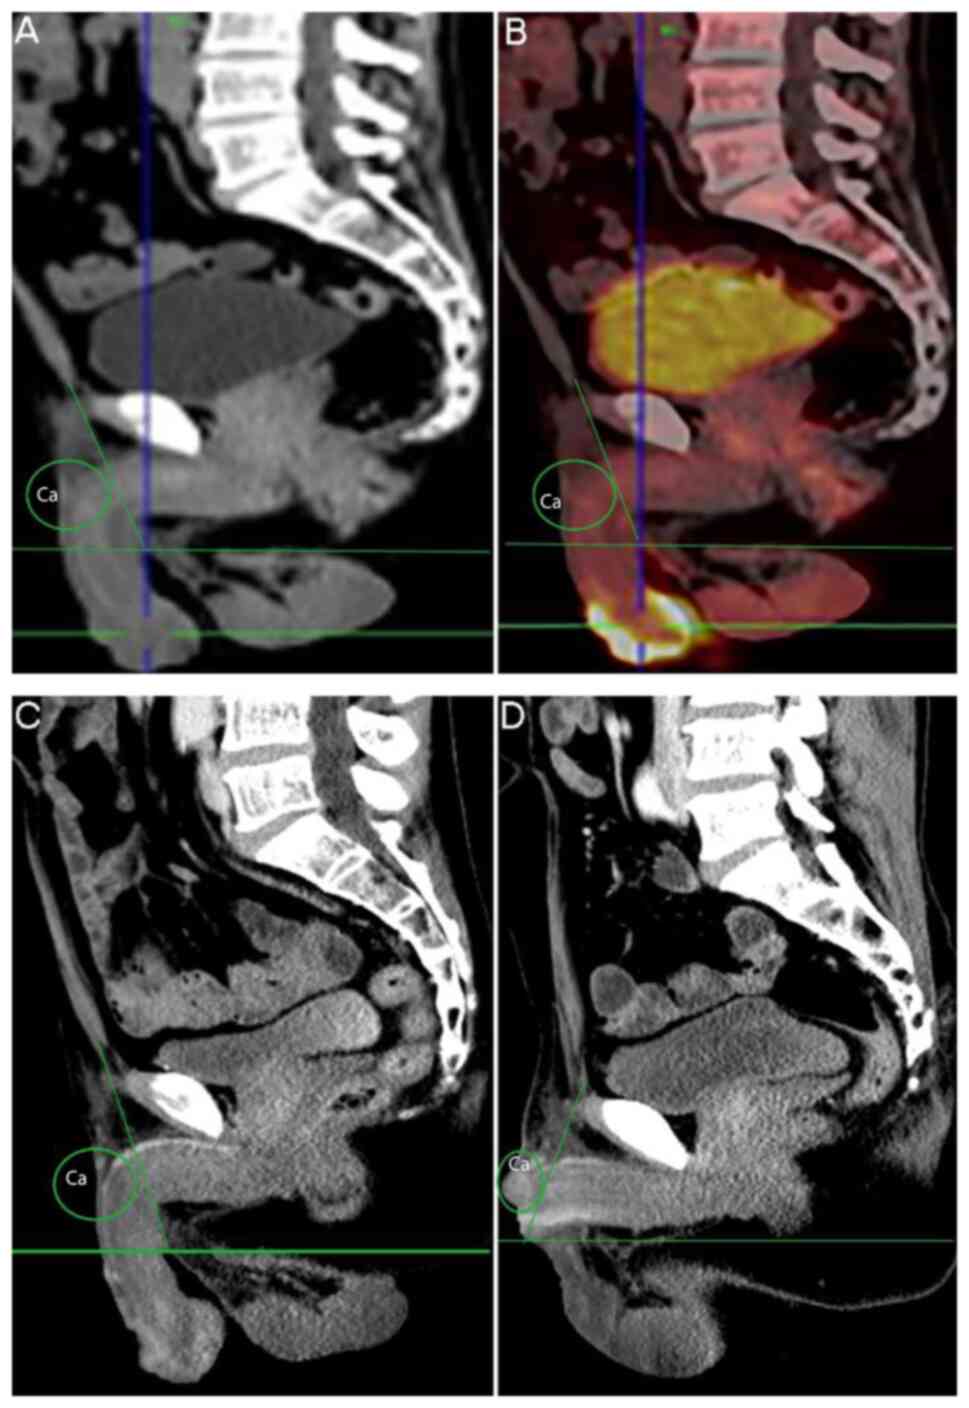

Case 2 (55-year-old). (A) Sagittal non-enhanced CT indicated multiple penile carcinomatous foci before partial penectomy (green circle indicates multiple penile carcinomatous foci). (B) Positron emission tomography/CT indicated multiple penile carcinomatous foci before partial penectomy (green circle indicates multiple penile carcinomatous foci). (C) Sagittal enhanced CT indicated multiple penile carcinomatous foci before partial penectomy (green circle indicates multiple penile carcinomatous foci). (D) Sagittal enhanced CT indicated recurrent cancer of the penile stump after partial penectomy (multiple penile carcinomatous foci were observed in the green circled area).

A 55-year-old male complained of a penile tumour that had recurred for one month in August 2018. The neoplasms had originally been resected 20 years previously. CT and PET/CT indicated metastasis of the bilateral inguinal and the left rib (Fig. 3A-D). SCC was confirmed after partial penectomy with unilateral inguinal lymph node dissection. The margin was negative (Table I).